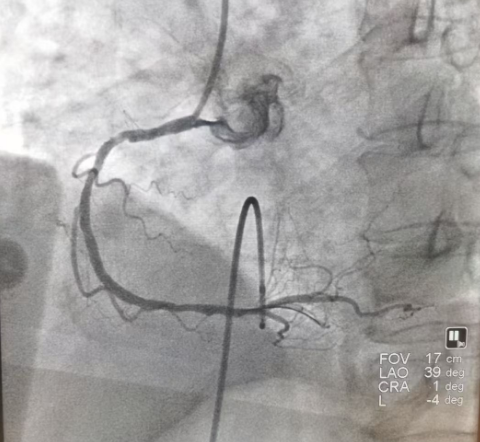

情况万分危急!瑞慈医院胸痛中心“绿色通道”立即启动。心血管内科崔勤主任团队火速会诊,结合心电图变化和症状,确诊老人是“急性下壁和右室心肌梗死,完全性房室传导阻滞”,当机立断:老人心跳这么慢,又有大面积心肌坏死,必须立刻做微创手术疏通堵塞的血管,这是救命唯一的办法!在快速征得家属同意后,崔勤主任团队制定了周密的方案:先给心脏装个临时的“起搏器”稳住心跳,接着立刻做心脏血管造影检查,如果需要就马上疏通血管。 △心血管内科崔勤主任(右一)团队术中 手术在导管室紧张进行,崔主任团队首先顺利在老人心脏里放置了一个临时“起搏器”,设定它每分钟发出60次电脉冲,代替坏掉的“电路系统”,暂时保住心跳。 刚放完临时起搏,患者再次出现心脏骤停,这次是室颤,患者瞬间意识丧失,团队成员迅速反应,立即启动心脏按压,电除颤,就在200J电流波迅速通过心脏,心律恢复。此时血压已然偏低,通过迅速的心脏血管造影,崔主任快速锁定病根——除了一根血管(左回旋支)也有多处严重狭窄外,另一根重要的血管(右冠状动脉)中间段完全堵死了!这根闭塞的血管就是导致心梗的“元凶”。 在临时起搏器的保护下,崔主任团队精准操作。用一根细如发丝的导丝小心翼翼地穿过了完全堵死的血管段,然后用小球囊把堵塞处撑开,最后精准放入一枚冠状动脉支架,血流完全恢复畅通! 崔勤主任提到,“这么大年纪的老人,心脏血管多处严重堵塞,加上心跳慢到随时会停,又突发心脏室颤,救活他就像走钢丝,风险极高。这次能成功,靠的是迅速判断,沉着应战,关键是稳定的技术发挥以及整个胸痛急救团队的完美配合。心脏血管堵住后,心肌细胞每分每秒都在死亡,我们必须跟时间赛跑,抢回生机!” 南通瑞慈医院心血管内科一直致力于提升对心脏急危重症的救治能力,通过建设规范的胸痛中心,不断优化抢救流程。这位高龄、高危、病情复杂老人的成功获救,正是医院强大综合实力的证明,也为南通及周边地区老百姓的心脏健康筑起了一道坚实的防线。